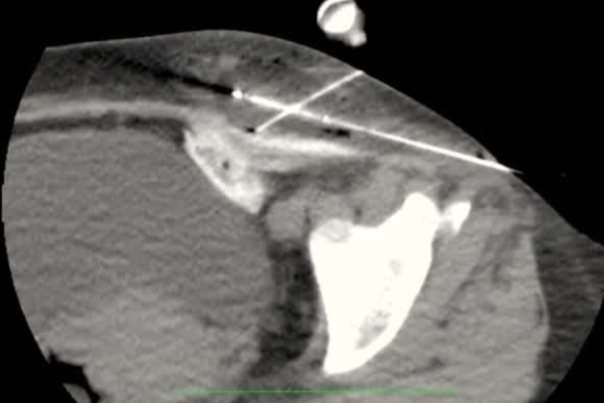

通常需要三根布针

隔离和布针

影像引导方式:超声和横断面成像(CT或MRI)结合是最常用的影像引导方式(10/16,62.5%)。

保护措施:几乎所有干预都需要辅助保护措施,其中水分离术(13/16,81.3%)和水分离术与温盐水填充手套的皮肤保护结合(9/16,56.3%)是最常见的保护措施。